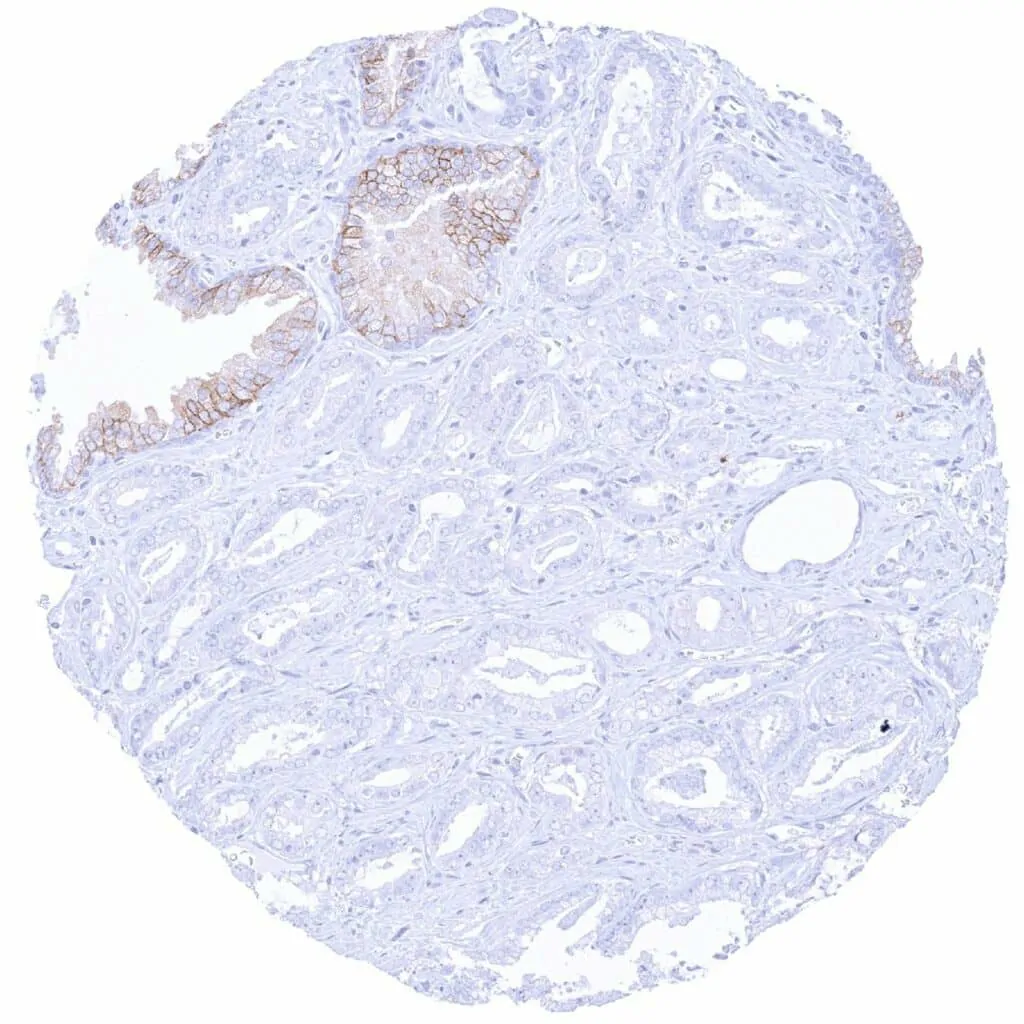

Prostate – CD38 negative adenocarcinoma (Gleason 3+3=6) adjacent to CD38 positive normal epithelium